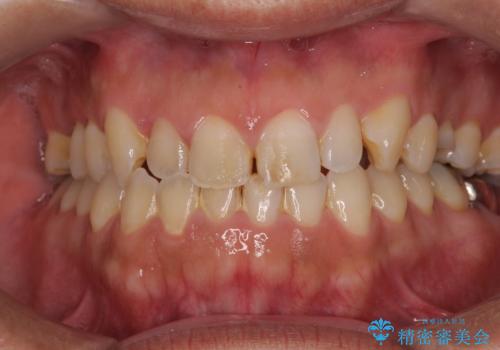

- 放置していたむし歯を治療したいとのことで来院された患者様です。

仕事が忙しいことを言い訳に虫歯を放置してきたものの、強い痛みを感じたことがあったため、重い腰を上げて来院されたとのことでした。

強い痛みのあった歯は、既に神経組織が失活しており根管治療が必要でした。

反対側の歯は、歯根だけが歯肉に埋もれて残っている状態のため、抜歯が必要な状態でした。